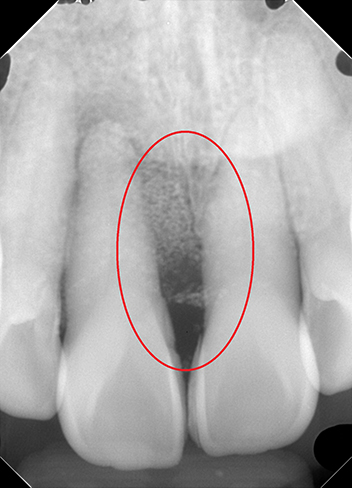

リグロス(歯周組織再生療法)の症例

年齢/性別が表示されたボタンを押すと、下部にスクロールして症例の画像と詳細をご覧になれます。